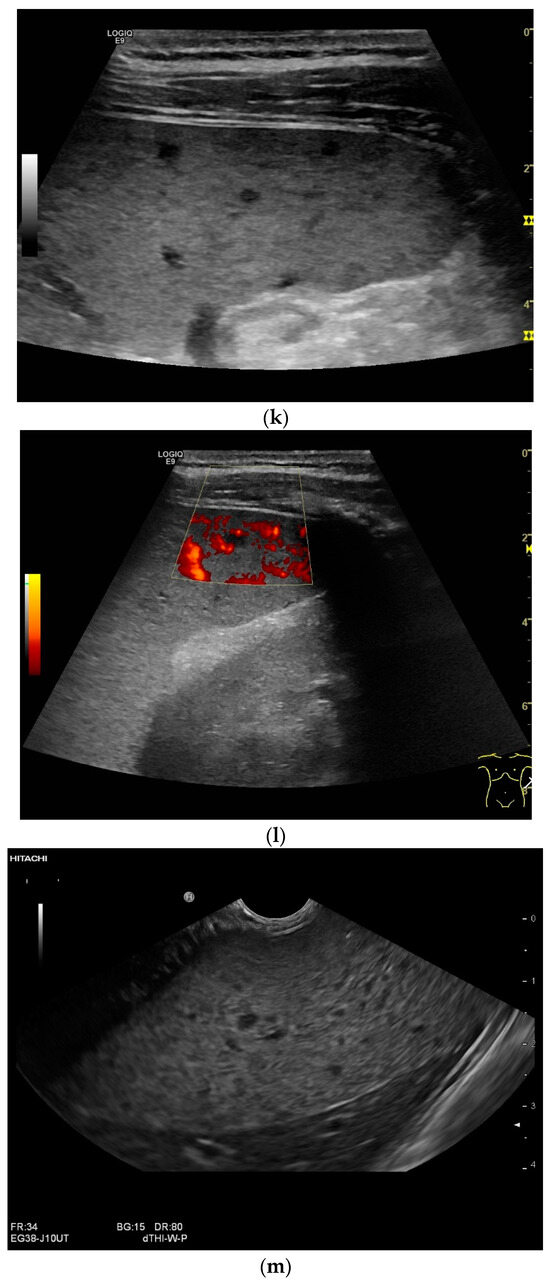

Figure 4.

Sonographic and CEUS features of splenic tuberculosis. Sonographic and CEUS features of splenic tuberculosis. Subcapsular splenic lesion (arrow) (a), subcapsular splenic lesion using a linear transducer of 12 MHz (arrows) (b). Histologically confirmed tuberculosis from mediastinal lymph nodes. Multiple small splenic lesions (c). Using CEUS with a linear transducer (9 MHz), these are slightly hypoenhanced in the arterial phase (d), and show a progressive washout in the course of the venous phase (arrows) (e). Subcapsular splenic lesion (arrow) with nonenhanced and hypoenhanced parts and hyperenhanced rims indicate a caseous necrosis (f). In another section, an interrupted spleen capsule (arrow) due to a rupture of the caseous necrosis can be assumed (g).

Spleen involvement usually only occurs in disseminated disease. The manifestations are splenomegaly, hypoechoic micronodular (miliary), or macronodular lesions [8,74], as well as splenic abscesses [75] [Figure 4a–d]. In a group of patients with tuberculosis and mostly advanced HIV infection, 37% had splenic lesions [5]. In 33%, splenic lesions were associated with lymphadenopathy, and 16% each had splenic lesions and ascites or splenic lesions, ascites, and lymphadenopathy. Micronodular lesions may be indistinguishable. If this is suspected, examination with a high-resolution linear transducer is recommended. Using CEUS, splenic lesions in the arterial phase showed a hyperenhancement, followed by either a slow washout or a persistent enhancement in the middle and late parenchymal phase [76]. A fast washout was the exception, but nevertheless was also possible. These exceptional cases would therefore be difficult to differentiate from malignancies. There was also rim-like enhancement with central nonenhancement, like abscesses and septation-like enhancement [76]. Another study using CEUS in splenic manifestations of tuberculosis presented homogeneous enhancement (6.7%), heterogeneous enhancement (63.3%), and nonenhancement (30.0%). Most of the cases showed low enhancement. Among these cases, heterogeneous enhancement was divided into septal enhancement type (21.1%) and marginal enhancement type (78.9%) [77] [Figure 4c–g]. The most important differential diagnoses are non-Hodgkin’s lymphoma and other granulomatous inflammations, such as sarcoidosis, especially in the presence of lymphadenopathy. The splenic lesions must be differentiated from mycotic abscesses, leukemic infiltrates, and metastases. In the meta-analysis conducted by van Hoving et al. [78], splenic lesions as manifestations of abdominal tuberculosis had a broad sensitivity of 13–62% in five studies using B-mode ultrasonography. The specificity was higher, at 86–100%.